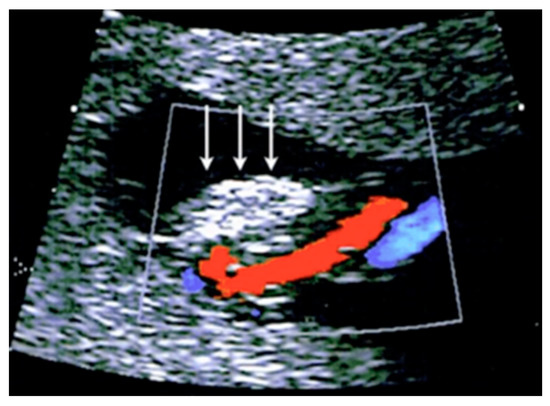

3.2.2. Vasa Praevia